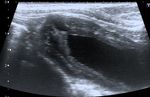

Figure 3. Longitudinal ultrasound image of the urinary bladder in a cat, showing the presence of a

small  (

diverticulum        was  made   at the  second    ultrasonography,     when   the bladder   appeared

the diagnosis of intramural vesicourachal diverticulum was made at the second ultrasonography,            less filled (Figure 7).

Therefore,     we   cannot   exclude   that  small   diverticula  may   be undiagnosed      by  the

when the bladder appeared less filled (Figure 7). Therefore, we cannot exclude that small diverticula use of ultrasonography,

(a)                                                             (b)

Figure

Figure7.7. Two

Twolongitudinal

longitudinalultrasound

ultrasoundimages

imagesofofthe

theurinary

urinarybladder

bladderofofaadog

dogwith

withanan intramural

intramural

vesicourachal

vesicourachaldiverticulum.

diverticulum.TheTheimages

imagesshow

showtwo

twodifferent

differentvolumes

volumesofofurine

urineinto

intothe

thebladder

bladderlumen.

lumen.

(a)Overly

(a) Overly distended:

distended: the

thediverticulum

diverticulumappears

appearsasas

a not very

a not    visible

very      focalfocal

visible   depression  in thein

depression    cranial-ventral

the cranial-

aspect of

ventral     the bladder,

aspect   of the with  thinning

bladder,  withofthinning

the correspondent    bladder wall;bladder

of the correspondent        (b) ddequately

wall; (b) distended:

ddequatelythe

diverticulum

distended:   theappears   as an evident,

diverticulum   appears focal,

as an evagination   in the

evident, focal,     cranio-ventral

evagination    in theaspect  of the bladder.

cranio-ventral   aspect of

the bladder.